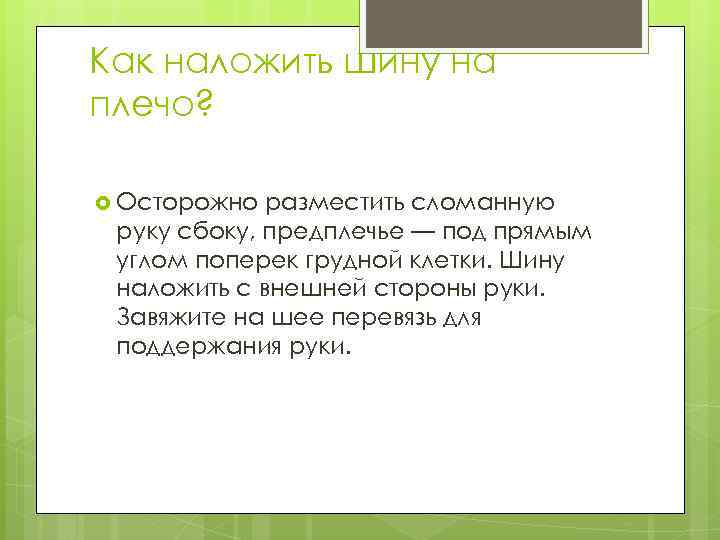

Как наложить шину на плечо? Осторожно разместить сломанную руку сбоку, предплечье — под прямым углом поперек грудной клетки. Шину наложить с внешней стороны руки. Завяжите на шее перевязь для поддержания руки.

Как наложить шину на плечо? Осторожно разместить сломанную руку сбоку, предплечье — под прямым углом поперек грудной клетки. Шину наложить с внешней стороны руки. Завяжите на шее перевязь для поддержания руки.